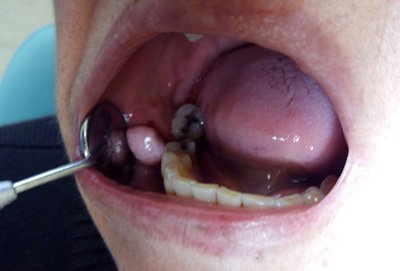

La hiperplasia se caracteriza por un agrandamiento difuso y relativamente avascular nodular o liso de las encías, que también puede cubrir los dientes. El tejido hipertrofiado a menudo debe extirparse. Si es posible, deben sustituirse los fármacos causantes. Una higiene bucal...